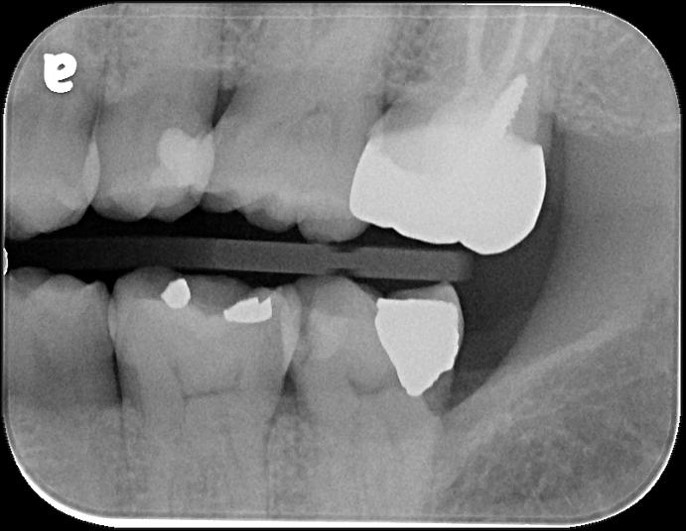

治療前,有銀粉復形,牙齒敏感

治療前,牙髓已接近被侵犯